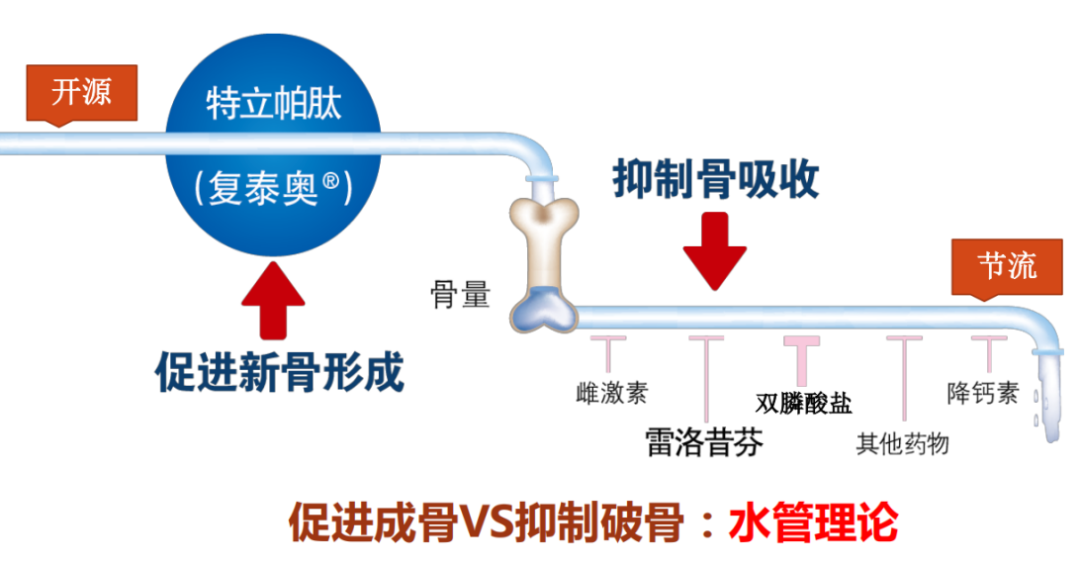

5.抗骨质疏松药物

对于已发生椎体脆性骨折的患者,无论其 DXA 骨密度检查结果是否达到诊断标准,都应进行抗骨质疏松症药物治疗。

(1.)骨吸收抑制药

双膦酸盐类:是目前临床上应用最为广泛的抗骨质疏松症药物。能抑制骨吸收,减少骨丢失,并有止痛作用。其作用机制是通过抑制体内破骨细胞活性,使骨转化率下降,从而减少骨质的丢失。

降钙素(CT)类:能抑制破骨细胞的生物活性和减少破骨细胞的数量, 可预防骨量丢失并增加骨量。

此外,CT还有较强的镇痛作用,尤其对老年性骨质疏松所致的腰腿痛、骨病引起的骨痛有特效,因而更适合有疼痛症状的骨质疏松症患者。一般给药 2~3周后疼痛可缓解,能减少其他镇痛药的用量。

选择性雌激素受体调节剂(SERMs):有效抑制破骨细胞的活性,降低骨转换至妇女绝经前水平,本品用于预防和治疗绝经后妇女的骨质疏松症,能显著地降低椎体骨折发生率。

雌激素类此类药物:只能用于女性患者。雌激素类药物能抑制骨转换,阻止骨丢失。

临床研究已充分证明雌激素或雌孕激素补充疗法(ERT或HRT)能降低骨质疏松性骨折的发生危险,是防治绝经后骨质疏松的有效措施。

(2.)骨形成促进药

①甲状旁腺激素类似物

以特立帕肽为代表,具有强大的促骨形成的作用,一般认为,其抗骨质疏松作用强于抗骨吸收药物。适用于绝经后、男性和糖皮质激素性骨质疏松症以及高骨折风险患者的治疗。